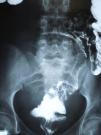

Enema examination of the colon showed that the cyst was exerting pressure on the small bowel-ileum and displacing the sigmoid colon to the left and backwards (Fig. 3).